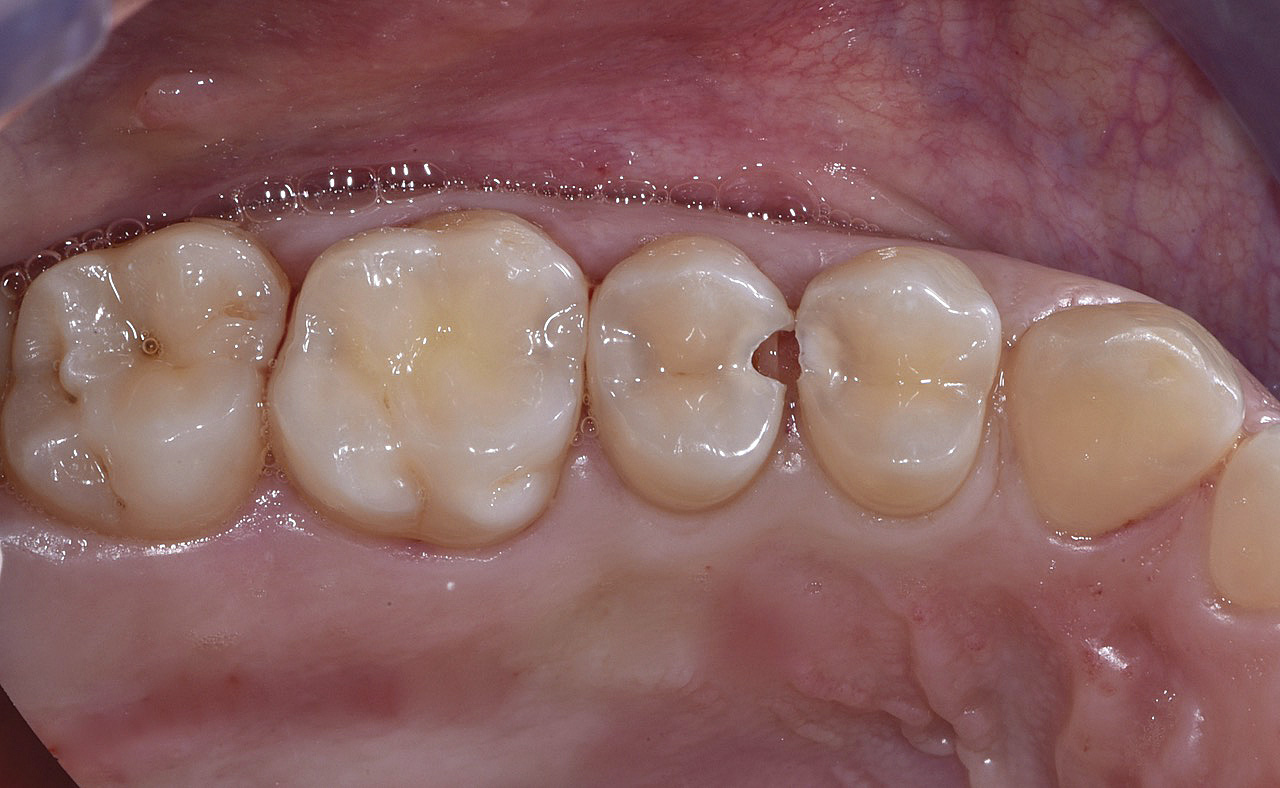

PREMESSA: in seguito all’estrazione dell’incisivo laterale superiore di destra, resasi necessaria per cause batteriche, si decide di affrontare il caso con il posizionamento di un impianto in sostituzione dell’elemento mancante dopo guarigione del sito infetto. Con tecniche rigenerative sia dei tessuti ossei mancanti a causa dell’infezione pregressa, sia dei tessuti gengivali che appaiono inizialmente troppo spostati in alto, si ripristina una corretta morfologia delle parabole (contorni) gengivali e delle papille interdentali (triangoli di gengiva tra due denti vicini).

Vengono utilizzati 2 tipi di provvisori: il primo, cementato ai denti vicini, viene utilizzato dal momento dell’estrazione del dente fino ad impianto osteointegrato (circa 6 mesi); il secondo, avvitato direttamente all’impianto, ha una funzione di prova estetica ma soprattutto di guida per la maturazione dei tessuti gengivali peri-implantari portandoli verso la maturazione completa prima di posizionare la corona finale in disilicato di litio.